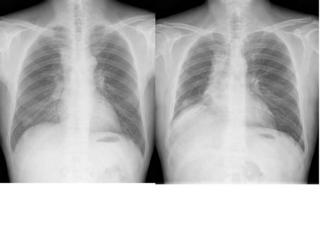

例えば肺の大きさ。

volume

lossや反対に過膨張などの所見は、圧倒的に胸部正面写真がわかりやすいですね。